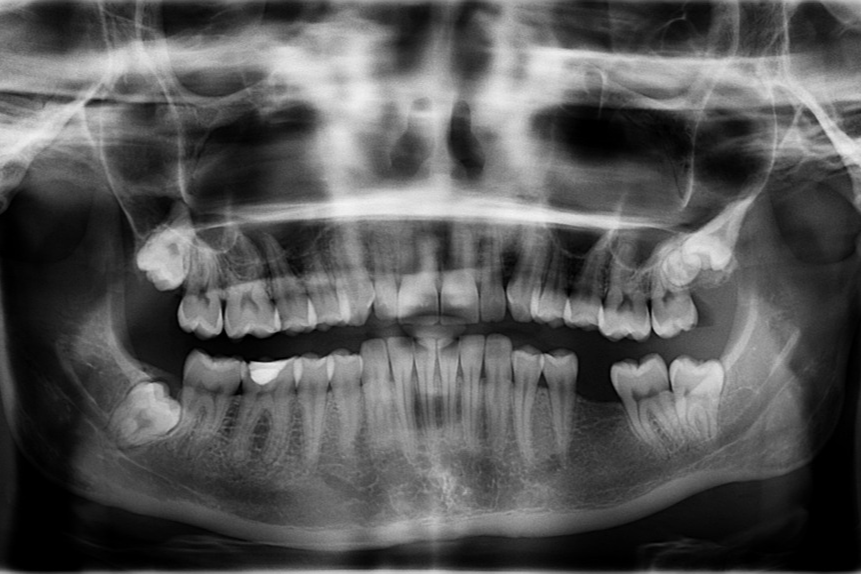

사랑니 상태는 개인마다 다르기 때문에 정기적인 치과 검진을 통해 상태를 확인하는 것이 중요합니다. X-ray 촬영을 통해 사랑니가 정확히 어떤 위치에 있고, 발치가 필요한지 판단할 수 있습니다.